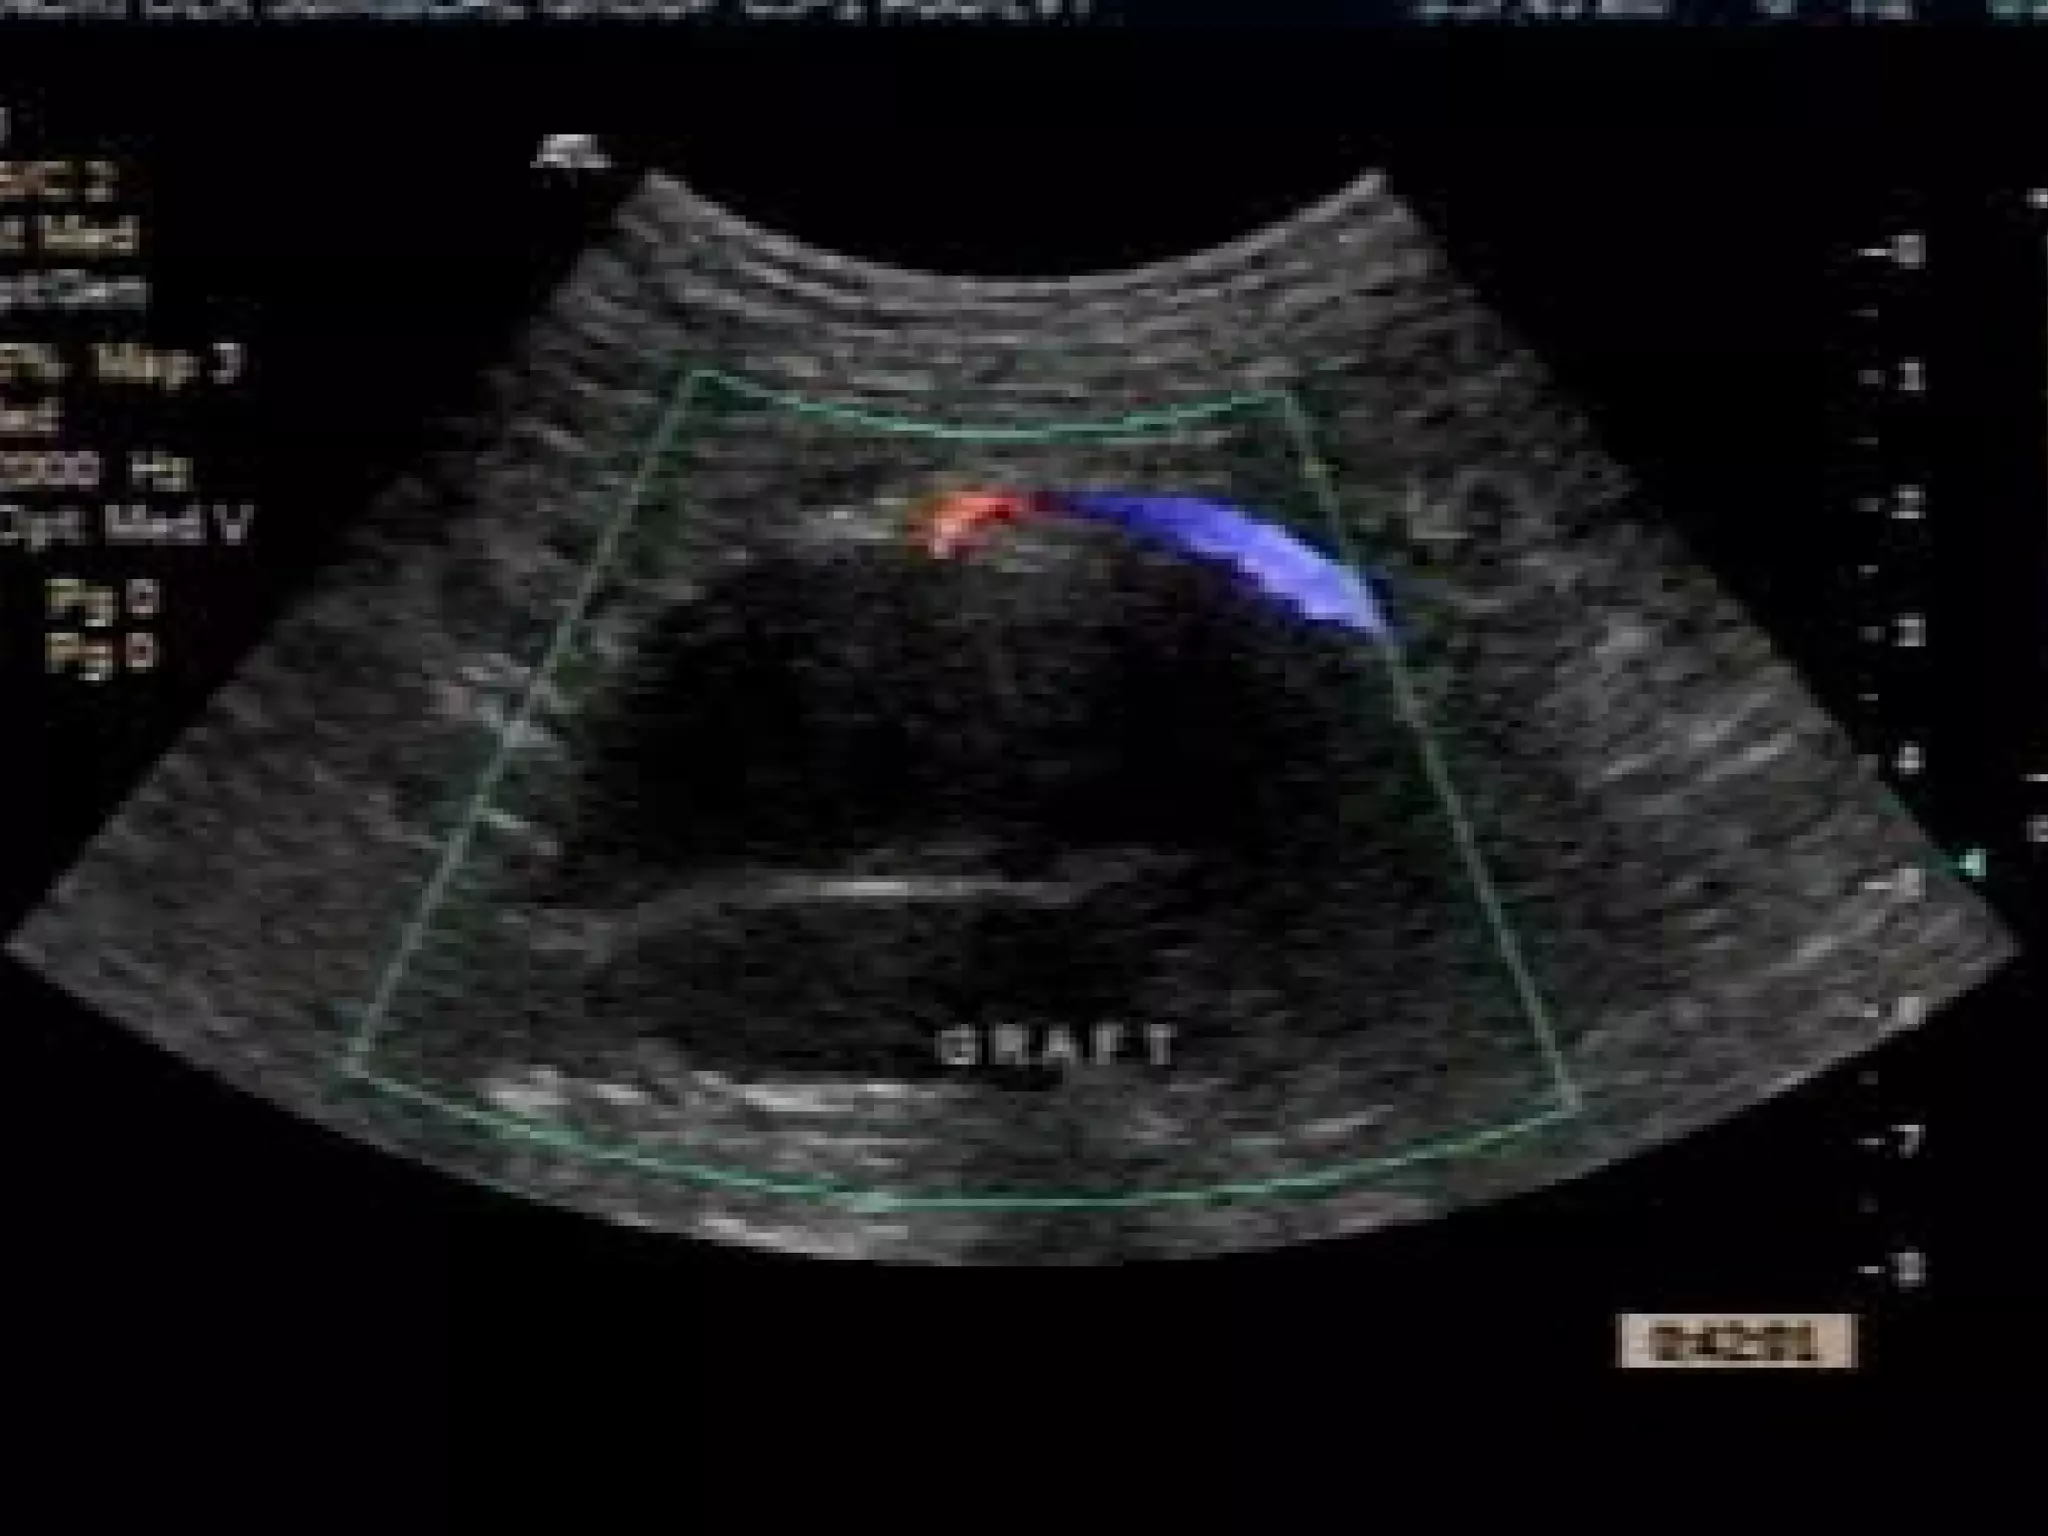

Lumbar Endoleak

Coils at

origin of Lumbar